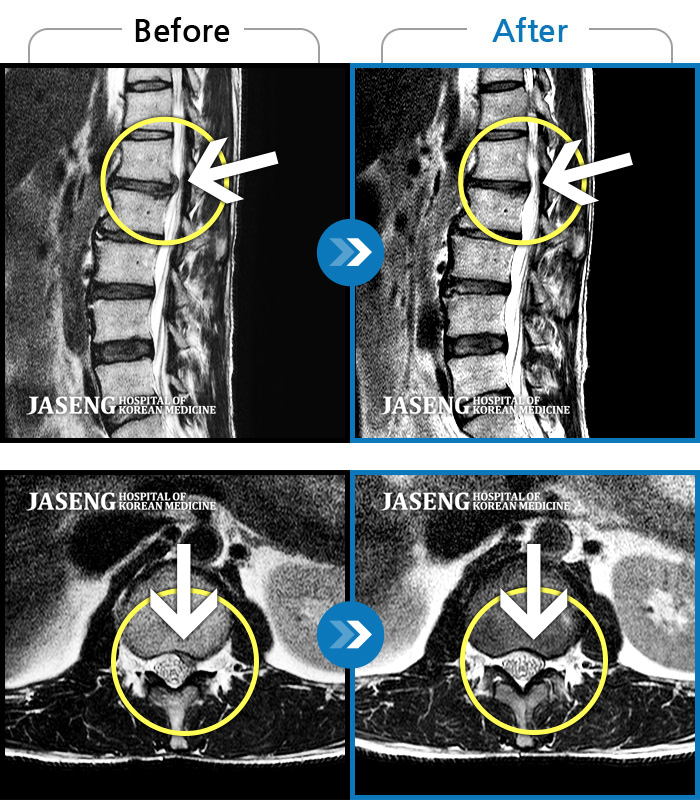

통증 및 우측 엉치 우측 종아리 땡기는 통증이 심하여 일상생활이 안되는 상태로 내원하셨던 분입니다.

2023.11.21 ~ 2024.06.05